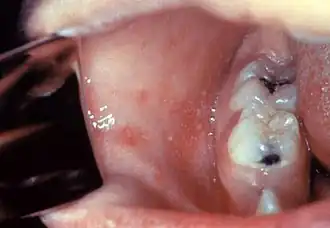

El periodo de incubación es de aproximadamente 4-12 días (durante los cuales no hay síntomas). El primer síntoma suele ser la aparición de fiebre alta, por lo menos tres días, tos, coriza (nariz moqueante) y conjuntivitis (ojos rojos). La fiebre puede alcanzar los 40 °C (104 °F). Las manchas de Koplik que aparecen dentro de la boca son patognomónicas (su aparición diagnostica la enfermedad), pero son efímeras: desaparecen en unas 24 horas.[cita requerida]